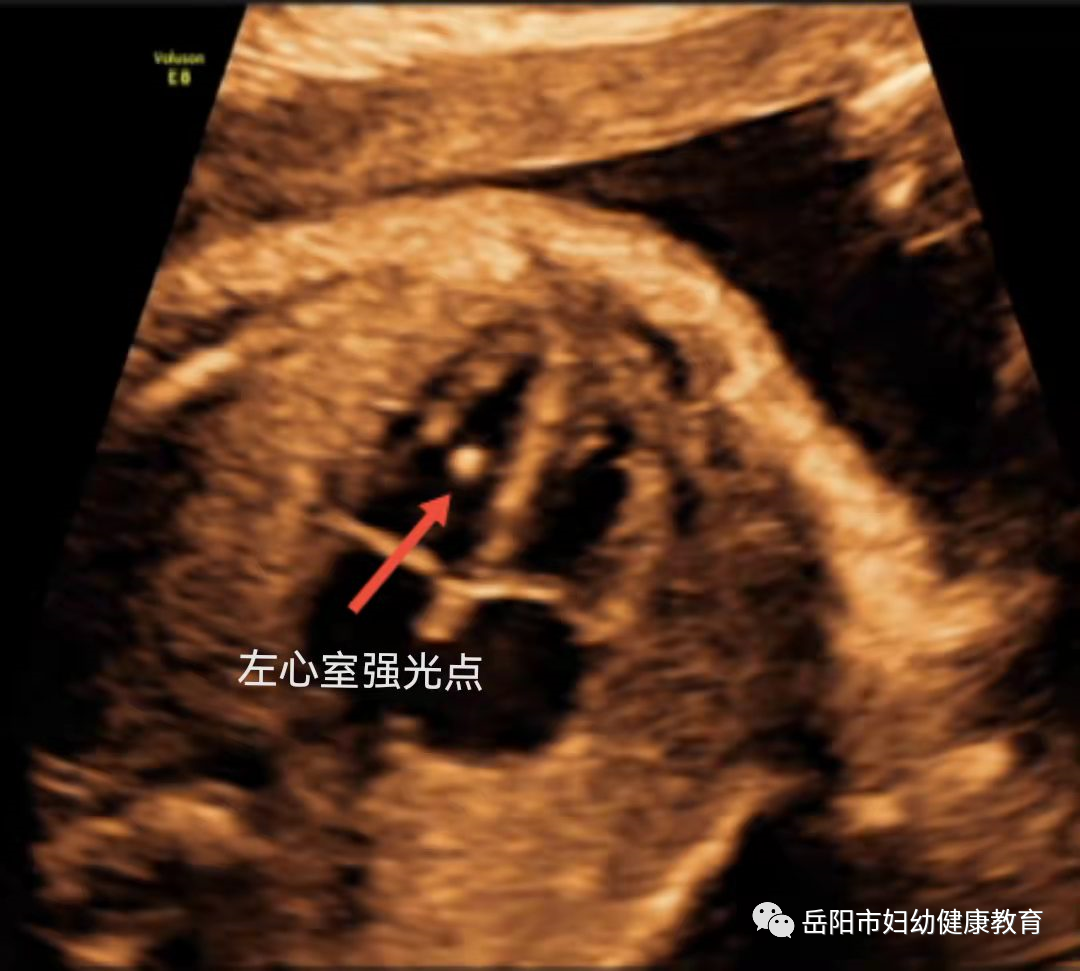

4、心室内强光点

心室内强光点

是指心室内出现的点状强回声,可单发也可多发,以左心室内常见。可能为心室内乳头肌的钙化,他不是心脏畸形,可随孕周的增加逐渐变弱甚至消失,也有的至出生时仍未消失,但这对宝宝并没有影响。

单纯的心室强光点与染色体异常相关性不大。唐氏筛查低风险的孕妈妈可忽略他的存在,而高龄孕妈妈发现心室内强光点可选择无创

DNA

检查,在合并有其他结构异常时,建议行产前诊断排除染色体异常。